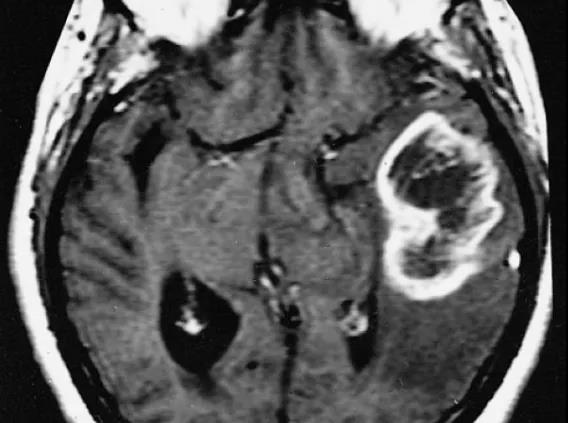

磁共振成像顯示多形性膠質(zhì)母細胞瘤。膠質(zhì)母細胞瘤腫瘤通常表現(xiàn)為“環(huán)狀”的強化,圍繞暗色的中央壞死區(qū)。

來源:Public Domain - The Armed Forces Institute of Pathology (US)